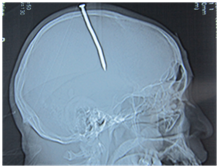

Figure 1 Sagittal X ray showing the full length of the nail in the cranium.

Unlike gunshot and missile injuries, the damage in low-velocity wounds is predominantly restricted to hemorrhagic infarctions along the wound track. They do not cause contrecoup injuries and diffuse axonal injury compared to motor vehicle accidents.7 Radiological investigation plays an important role in the identification of the stabbing object. In any patients with intracranial penetrating wounds, skull X-rays, subsequent CT scan and possibly cerebral angiography should be obtained.8 In low socioeconomic settings the inaccessibility of a CT scan should not delay the surgical evaluation if the weapon is identified on x ray, depending on the site of penetration and physical morphology of the penetrating object.